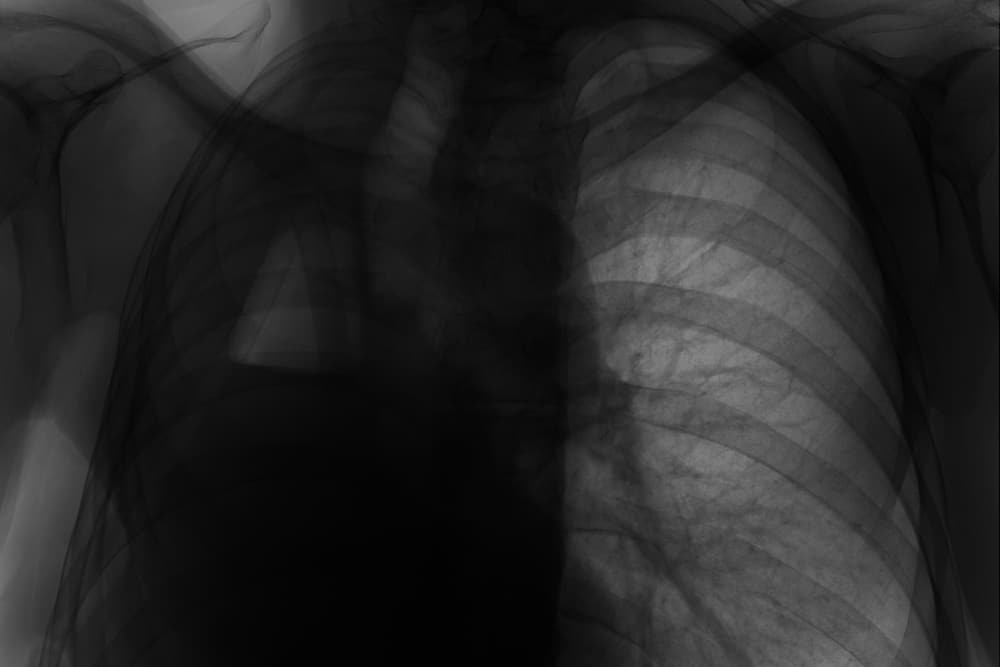

Pneumonectomy or Lung Removal: Can You Live With Only One Lung?

A lung removal operation may sound shocking or scary to most people. Is it possible? Can you live with only one lung? While every operation has risks or may potentially be life-threatening, some operations such as a pneumonectomy, or lung removal, are necessary.

A pneumonectomy is a surgical procedure wherein a lung removal is performed by a set of doctors and surgeons. This is typically done as part of lung cancer treatment.

Lung removal is generally performed by doctors as a treatment for particular lung cancer patients. These persons should have no indication of cancer spreading outside of the lungs. They also need to be strong enough to endure the procedure.